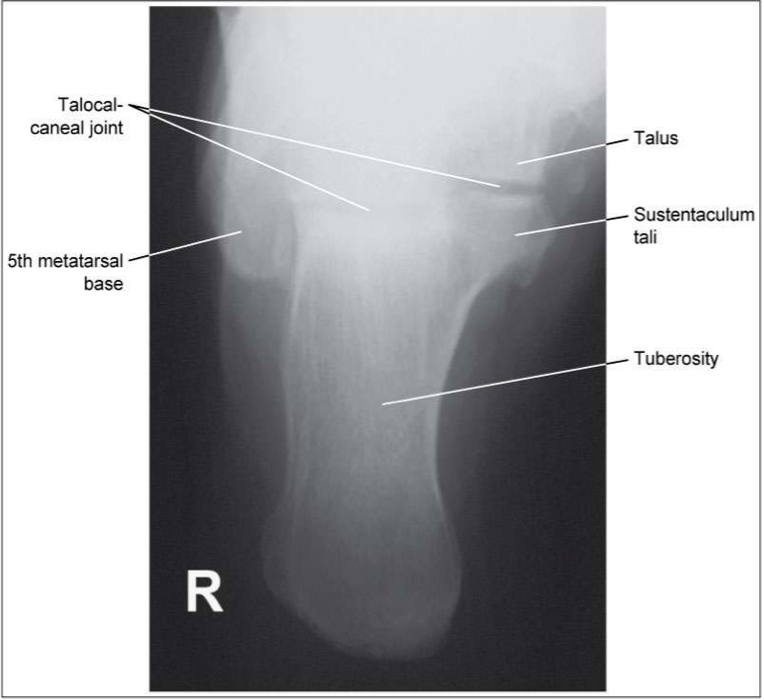

Plantodorsal Axial Calcaneus

Evaluation Criteria of plantodorsal axial calcaneous

• Entire calcaneous visualized

• Including open talocalcaneal joint space

• No rotation

• Base of the 5th MT seen laterally

• Sustentaculum tali visible in profile medially